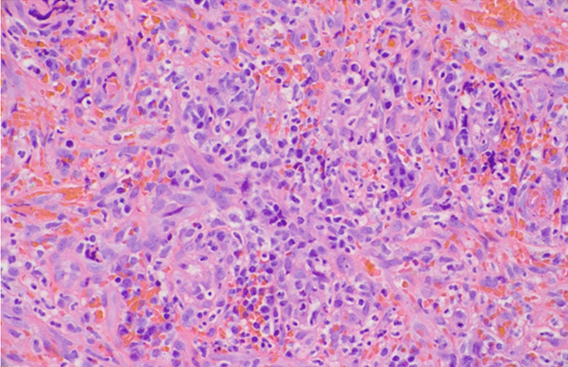

Colonoscopy revealed a normal cecum, ascending, transverse, descending, and sigmoid colon. A non-obstructing, circumferential, friable, ulcerated, nodular mass was seen from the dentate line to 14 cm (Figure 1). Multiple forceps biopsies were taken and the proximal margin of the mass was tattooed. Biopsy histology revealed ulcerated tissue with a granulation tissue like appearance, though a proliferation of bland spindle cells without increased mitotic activity was also seen (Figure 2). Human herpesvirus 8 (HHV-8) positive endothelial cells were noted within these spindle cells (Figure 3) and overall morphology was diagnostic of KS. Background rare spirochetes were identified, consistent with the patient’s known Treponema pallidum (syphilis) infection. Of note, within the mixed inflammatory infiltrate were some larger lymphocytes and increased atypical-appearing plasma cells along with scattered Epstein–Barr virus (EBV) positive cells. However, given the absence of a distinct clonal population by flow cytometry or immunohistochemistry, these latter findings were felt to be more in keeping with a reactive process rather than an EBV-driven lymphoproliferative disorder. The specimen was negative for granulomata or carcinoma.

Figure 2: Hematoxylin and eosin (H&E) stain of rectal mass at high power comprised of a proliferation of bland spindle cells in a mixed inflammatory background with an overall granulation tissue-like appearance. Many extravasated red blood cells are seen.